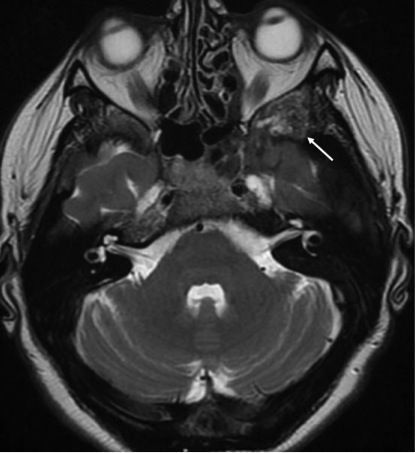

- МРТ головного мозга с внутривенным контрастированием: Аденома гипофиза с супраселлярным распространением. МР-картина фиброзной остеодисплазии. Субтотальное сужение наружных слуховых проходов, сужение зрительных каналов на уровне верхней глазничной щели (рис. 10, 11).

Рис. 10. МРТ головного мозга пациента И. Аденома гипофиза (белая стрелка).

Описание. Полость турецкого седла деформирована — сужена в переднезаднем размере. В полости турецкого седла, в супраселлярной цистерне имеется солидное объемное образование неоднородной структуры, размерами 9×16×9 мм. Образование смещает и компримирует хиазму.

Рис. 11. МРТ головного мозга пациента И. Очаги фиброзной дисплазии в затылочной кости (серая стрелка).

Описание. Асимметричная деформация костей черепа, преимущественно лицевого черепа, деформация костей основания черепа, выраженная деформация затылочной кости (серая стрелка), деформация тела и крыльев клиновидной кости; имеется полная облитерация лобных пазух, правой верхнечелюстной пазухи, пазух основной кости, частичная облитерация решетчатой кости, левой верхнечелюстной пазухи, сужение наружных слуховых проходов. Структура костей изменена по типу фиброзной дисплазии.